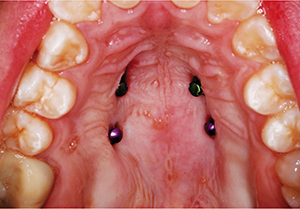

Four TADs were placed in the palate for the skeletal anchorage necessary for the expansion of the maxilla (Fig. 9). After the TADs were placed, an impression was taken for an acrylic skeletal expander that was supported solely by the palatal TADs. The appliance was delivered and fixed in place using a resin-modified glass ionomer. After cementation of the appliance had occurred, the patient was instructed to turn the appliance one time per day for two weeks and then return for evaluation, at which point one turn per day was continued with weekly evaluation. A total of 42 turns were completed over the course of six weeks for a total amount of 10.5 mm of expansion. At that time it was determined that no additional expansion was necessary. During the expansion phase of treatment, no bands or brackets were placed.

Fig. 9